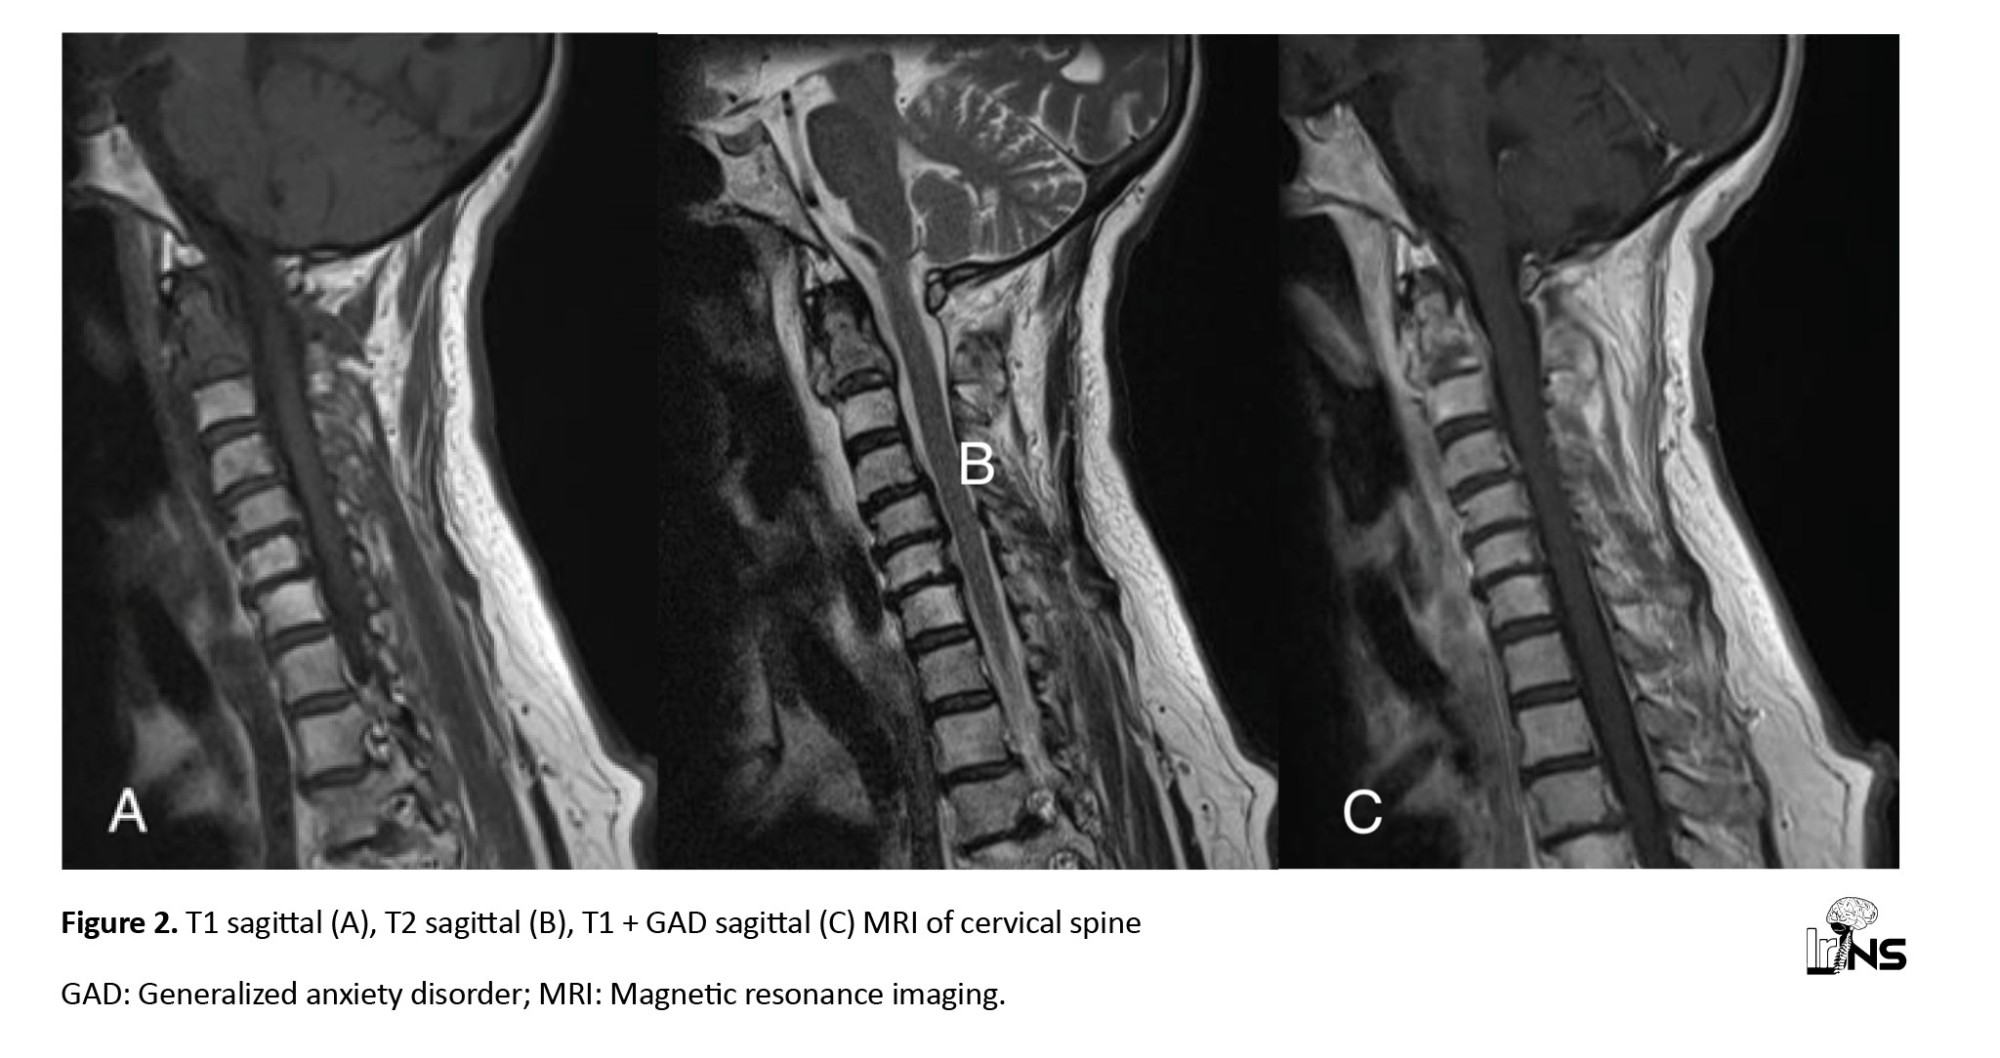

Furthermore, magnetic resonance imaging (MRI) showed hypo-signal lesions in the T1 sequence and hyper-signal in T2 with heterogenous enhancement in T1 + generalized anxiety disorder (GAD) (

Figure 2).

Histological findings, including identifying monoclonal plasma cell infiltrates, are essential to establish a primary diagnosis. Our patient exhibited a lytic lesion on both MRI and CT, indicative of a malignant tumor. The CT showed expansive bone destruction, preserving the anterior and posterior borders. Patients presenting with tumor-induced pain may be good candidates for palliative therapies, such as radiation or bisphosphonate treatment, depending on the primary tumor type [12]. Our patient’s pain was mechanical and caused by craniocervical instability resulting from a pathologic fracture. After a comprehensive whole-body metastatic assessment, the primary tumor remained undiagnosed. Consequently, we opted for an invasive treatment approach as the patient was in good overall condition but symptomatic.